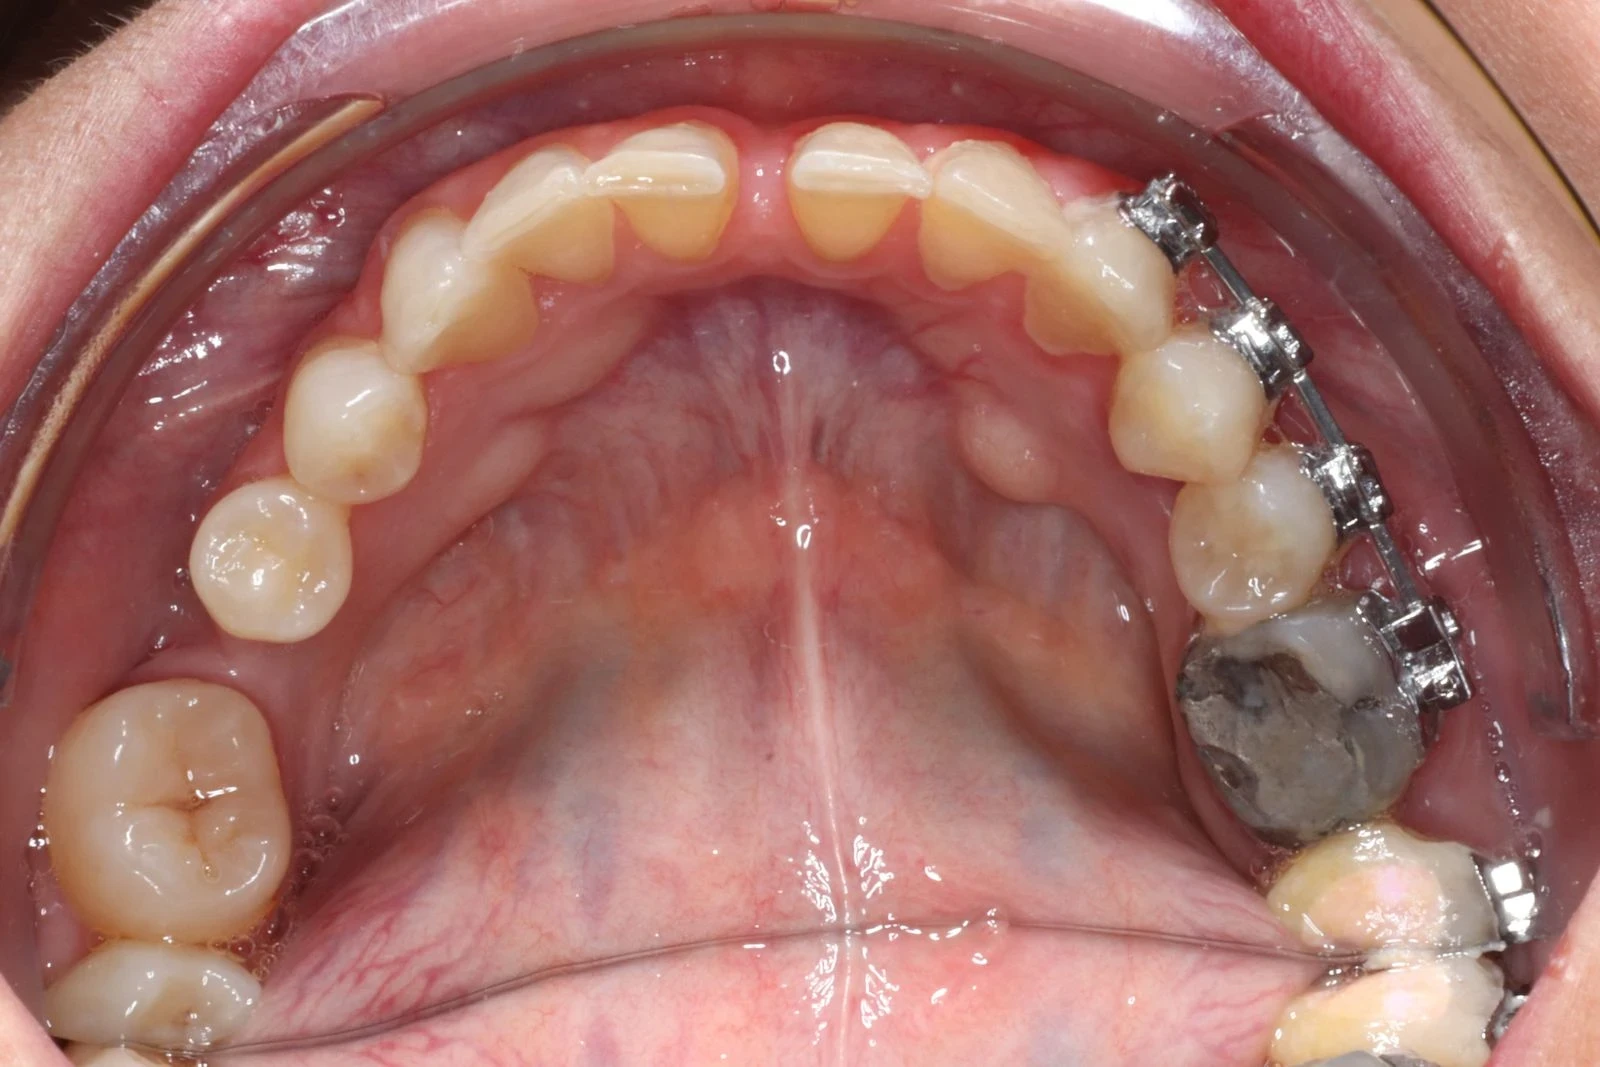

L'orthodontie linguale

La correction invisible par excellence

L’orthodontie linguale se différencie des traitements multibagues traditionnels, du fait de son emplacement : les bagues et les fils sont installés sur la surface interne des dents, du côté de la langue, rendant ainsi le traitement invisible.

C’est pour cela que cette technique d’orthodontie séduit de plus en plus de patients adultes, désireux d’embellir leur sourire sans que personne ne le sache.

Ce traitement n’est pas réservé à l’adulte : le Dr Christophe MAYODE pourra le prescrire à des adolescents, désireux de bénéficier d’un traitement d’orthodontie invisible.

À savoir :

À la fin de chaque traitement d’orthodontie linguale, le Dr C. MAYODE prévoit une double contention, incluse dans le traitement, afin de garantir la stabilité de ce dernier dans le temps.